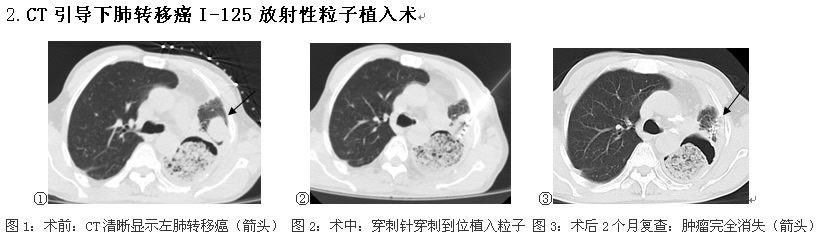

上图所示为一个食管癌术后左肺上叶转移的患者,无再次外科手术指征,化疗效果亦不佳。附一医院介入科通过一种微创的介入手术可以治疗这种转移癌——使用一枚或多枚直径仅为1mm的空心针,通过CT的引导经皮肤穿刺到达肿瘤所在的位置,然后把附带植入“针”的粒子枪与空心针连接进行粒子植入,“针”会将粒子枪中的125I放射性粒子植入到肿瘤中,通过125I放射性粒子释放能量——发射低能γ射线和特征性X射线,把肿瘤细胞直接杀死。